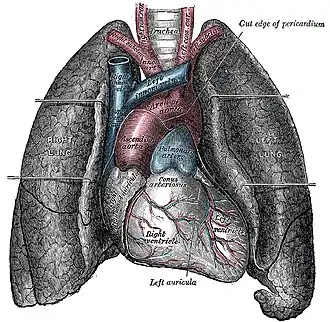

Грудна́я по́лость (лат. cavum thoracis) — анатомическое пространство, ограниченное внутренней поверхностью грудной клетки и верхней поверхностью диафрагмы. Стенки грудной полости выстилает внутригрудная фасция (лат. fascia endothoracica). Центральные отделы грудной полости заняты средостением, по бокам от которого расположены лёгкие. Лёгкие со всех сторон окружены щелевидными плевральными полостями, сформированными висцеральным (внутренним) и париетальным (наружным) листками плевры.